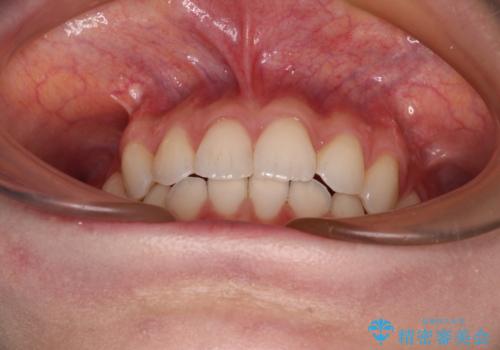

前歯のデコボコと深い咬み合わせ インビザラインできれいに改善

インビザラインは、装着していない時間がどれだけ短いかが、治療期間を大きく左右します。こちらの患者様は1日22時間以上、毎日欠かさず装着してくださったため、1年弱という短期間で満足のいく歯列に整えることができました。